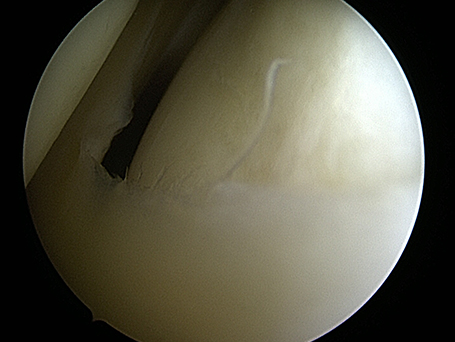

Bild Knie nach Arthroskopie

Knie nach Arthroskopie

Innenmeniskuseinrisse durch Verschleißleiden mit belastungsabhängiger innenseitiger Symptomatik. Intraoperativ deutliche Zerfaserung des gesamten Randes des Innenmeniskus insbesondere im Hinterhornbereich. Nach arthroskopischer Säuberung glatter stabiler Restmeniskus bei nur geringem Knorpelschaden. Außenseitiges Gelenk ohne Zeichen des vorzeitigen Verschleißes. Nach dem ambulanten Eingriff ist eine schmerzadaptierte Belastung an Gehstützen erlaubt. Regelmäßiges Kühlen. Die meisten Patient*innen können nach 10 - 14 Tagen schon eine alltagstaugliche Belastung des Kniegelenkes durchführen.

Bild gesäuberte Meniskuskante

Gesäuberte Meniskuskante